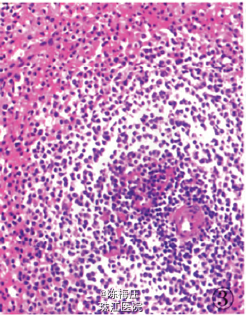

初步诊断:子宫肌瘤,子宫腺肌病,盆腔多发肿物性质待查。 确定诊断:盆腔腹膜脾组织植入。 完善相关检查,行全子宫切除术。病理检查:眼观:全切子宫1个,13 cm×8 cm×5.5 cm大小,子宫做多个切面,在肌层内查见2个大小不等灰白色肌瘤,肌瘤面积O.3 em×0.2 cm—l cm×0.66cm,肌瘤切面质韧,灰白色,呈编织状,边界清;内膜光滑,厚0.2—0.3 em,肌层厚2.5—3.5 cm,部分呈海绵状,子宫颈光滑,切面质韧,质地较细。盆腔内不规则肿物1个,灰红色,表面结节状,11cm×7.5 cm×3.5 cm大小,做多个切面,切面见多个结节,结节面积:0.4cm×0.3 cm~4.3 cm×2.5 cm,结节切面质脆,灰红色,质地细,结节边界清。另送圆形结节5个,直径1~3 cm不等,切面性质同盆腔较大肿物,均有包膜(图1)。镜检:患者子宫检查为子宫肌瘤,子宫腺肌病,病变无特殊性。盆腔多个肿物病变性质基本一致,为扩张血窦样组织,窦腔内充满红细胞,似脾红髓淤血(图2),在血窦样组织间有大小不等、发育良莠不齐的白髓样结节,结节较大者有小中央动脉(图3),结节较小者中央动脉不明显,内皮细胞无异型性,细胞分化均无异性,无病理性分裂象。可见玻璃变性纤维结缔组织似脾小梁样结构(图4)。免疫表型:血窦样内皮细胞nFli-1强阳性(图5),CD31弱阳性;CD34肿物小血管强阳性而血窦内皮细胞阴性(图6),CR和SMA均阴性;Ki-67增殖指数为5%。